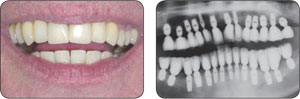

“根管治疗”是针对牙齿、牙髓、根尖病变的一个治疗过程。具体来讲,牙齿根管治疗是通过清除根管内的坏死物质,进行适当的消毒,充填根管,以去除根管内容物对根尖周围组织的不良刺激,防止发生根尖周病变或促进根尖周病变愈合的一种治疗方法。